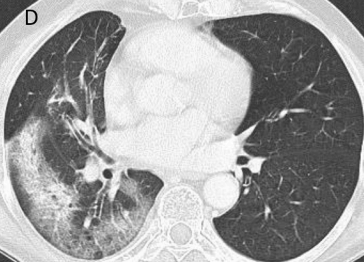

13.07.2025 Radioterapia stereotaktyczna nieoperacyjnego, centralnie zlokalizowanego NDRP- wyniki badania EORTC 22113-08113 LungTech phase II